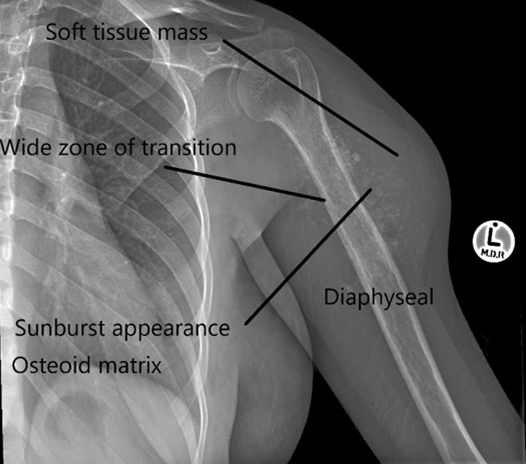

Anterior-Posterior (AP) X-ray of the patient’s left upper arm and shoulder showing a diffuse lytic lesion in its shaft/ diaphysis extending in a centrifugal (in all directions) manner.

Working from the outside in, there is extensive soft tissue extension from the bone, the matrix of the lesion shows cloud-like / ill-defined amorphous ossification in parts. There is a wide zone of transition between the normal bone and diseased bone, meaning that the border between them is not easily defined. The lesion is lytic in nature giving the humerus a moth-eaten appearance.

These are all features of a malignant bone sarcoma.